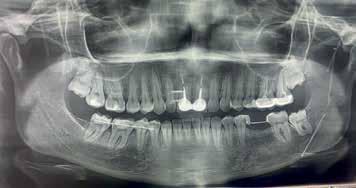

A 24-year-old female presented to the orthodontic clinic with the chief complaint of “Presence of space in the posterior mandibular right region”.

An intra- oral examination revealed the absence of the mandibular right first molar, tilting and oblique inclination of the mandibular second and third molar.

The patient had skeletal and dental class I, a normal overbite an overjet, slight mandibular anterior crowding, rotation of lower right first and second premolars, impaction of upper left and right third molars, and mandibular left third molar.

The patient recalls an extraction that was carried out during childhood but couldn’t specify exactly if it was the mandibular right first molar.

A panoramic x-ray showed the absence of the right first mandibular molar, a 45 degrees inclination of the second and third mandibular right molars, a vertical bone defect at the old extraction site, with a large composite filling on a endodontically treated mandibular left first molar.